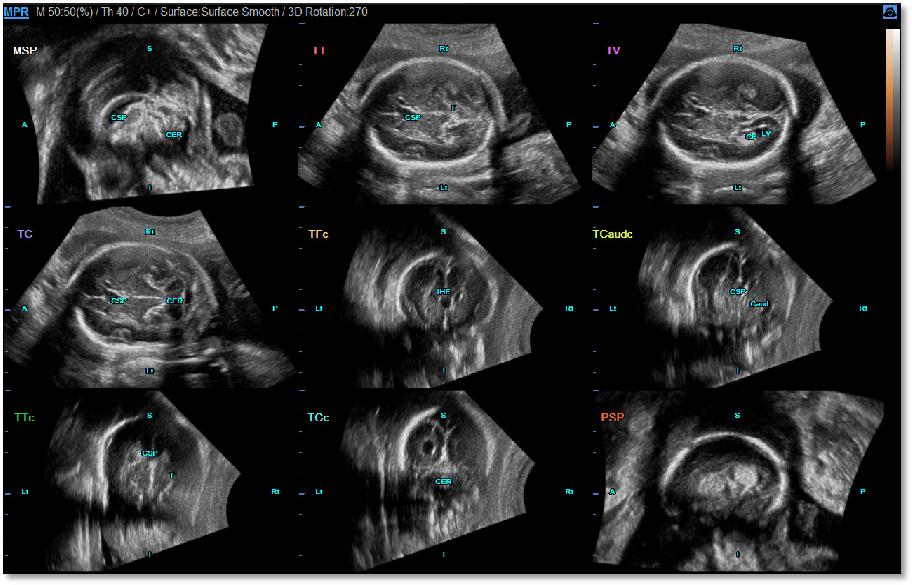

5D CNS+

根据 ISUOG 胎儿颅脑检查指南,自动获取标准检查切面。All 9 planes for fetal brain diagnosis

利用三维容积数据自动显示出ISUOG要求的9个切面。包括横切面、矢状面和冠状面等。